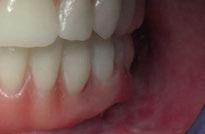

Presentamos el tratamiento rehabilitador de una paciente, realizado íntegramente en una sesión. Para este caso se ha utilizado un protocolo quirúrgico digital y guiado mediante la Plataforma de Planificación Bego Guide. Asimismo, se ha diseñado digitalmente una prótesis de carga inmediata atornillada e impresa con resina Bego VarseoSmile TriniQ®. Por lo tanto, se trata de un caso cuyo tratamiento precisa diferentes fases, pero efectuadas, todas ellas, el mismo día. De forma sencilla y cómoda para la paciente y el odontólogo, se ha obtenido una rehabilitación fija, funcional y estética. Palabras clave: Cirugía guiada, implantología oral guiada, cirugía sin colgajo, férula quirúrgica, rehabilitación fija maxilar, impresión digital, escáner intraoral, implantes dentales.

aproximadamente una hora y media. Usamos resina Bego VarseoSmile TriniQ® para puentes definitivos. Aunque en este caso la vamos a usar para confeccionar unas prótesis fijas atornilladas provisionales de larga duración, dado al aumento de dimensión vertical que vamos a realizar a la paciente, de esta forma obtendremos una neuroprogramación de la ATM reinstaurando una Dimensión Vertical apropiada y mejorando la estética facial de la paciente. Excluimos de la carga aquellos implantes que no obtuvieron una estabilidad primaria superior a 35 N/ cm2. El material permite la realización de una carga inmediata en material definitivo en puentes (Figuras 31 a 38).

Figura 37. Resultado final visión frontal. Figura 38. Resultado final visión lateral.

Finalmente nos sorprendió la pronta recuperación de la paciente, refiriendo un mínimo dolor percibido (más bien descrito como mínimas molestias), sin apenas precisar analgésicos ni antiinflamatorios postoperatorios (salvo en las primeras 12 horas), distando mucho del postoperatorio estándar en casos de cirugía convencional (13).

• De forma sencilla y cómoda para la paciente y el odontólogo, se obtiene una rehabilitación fija, funcional y estética.